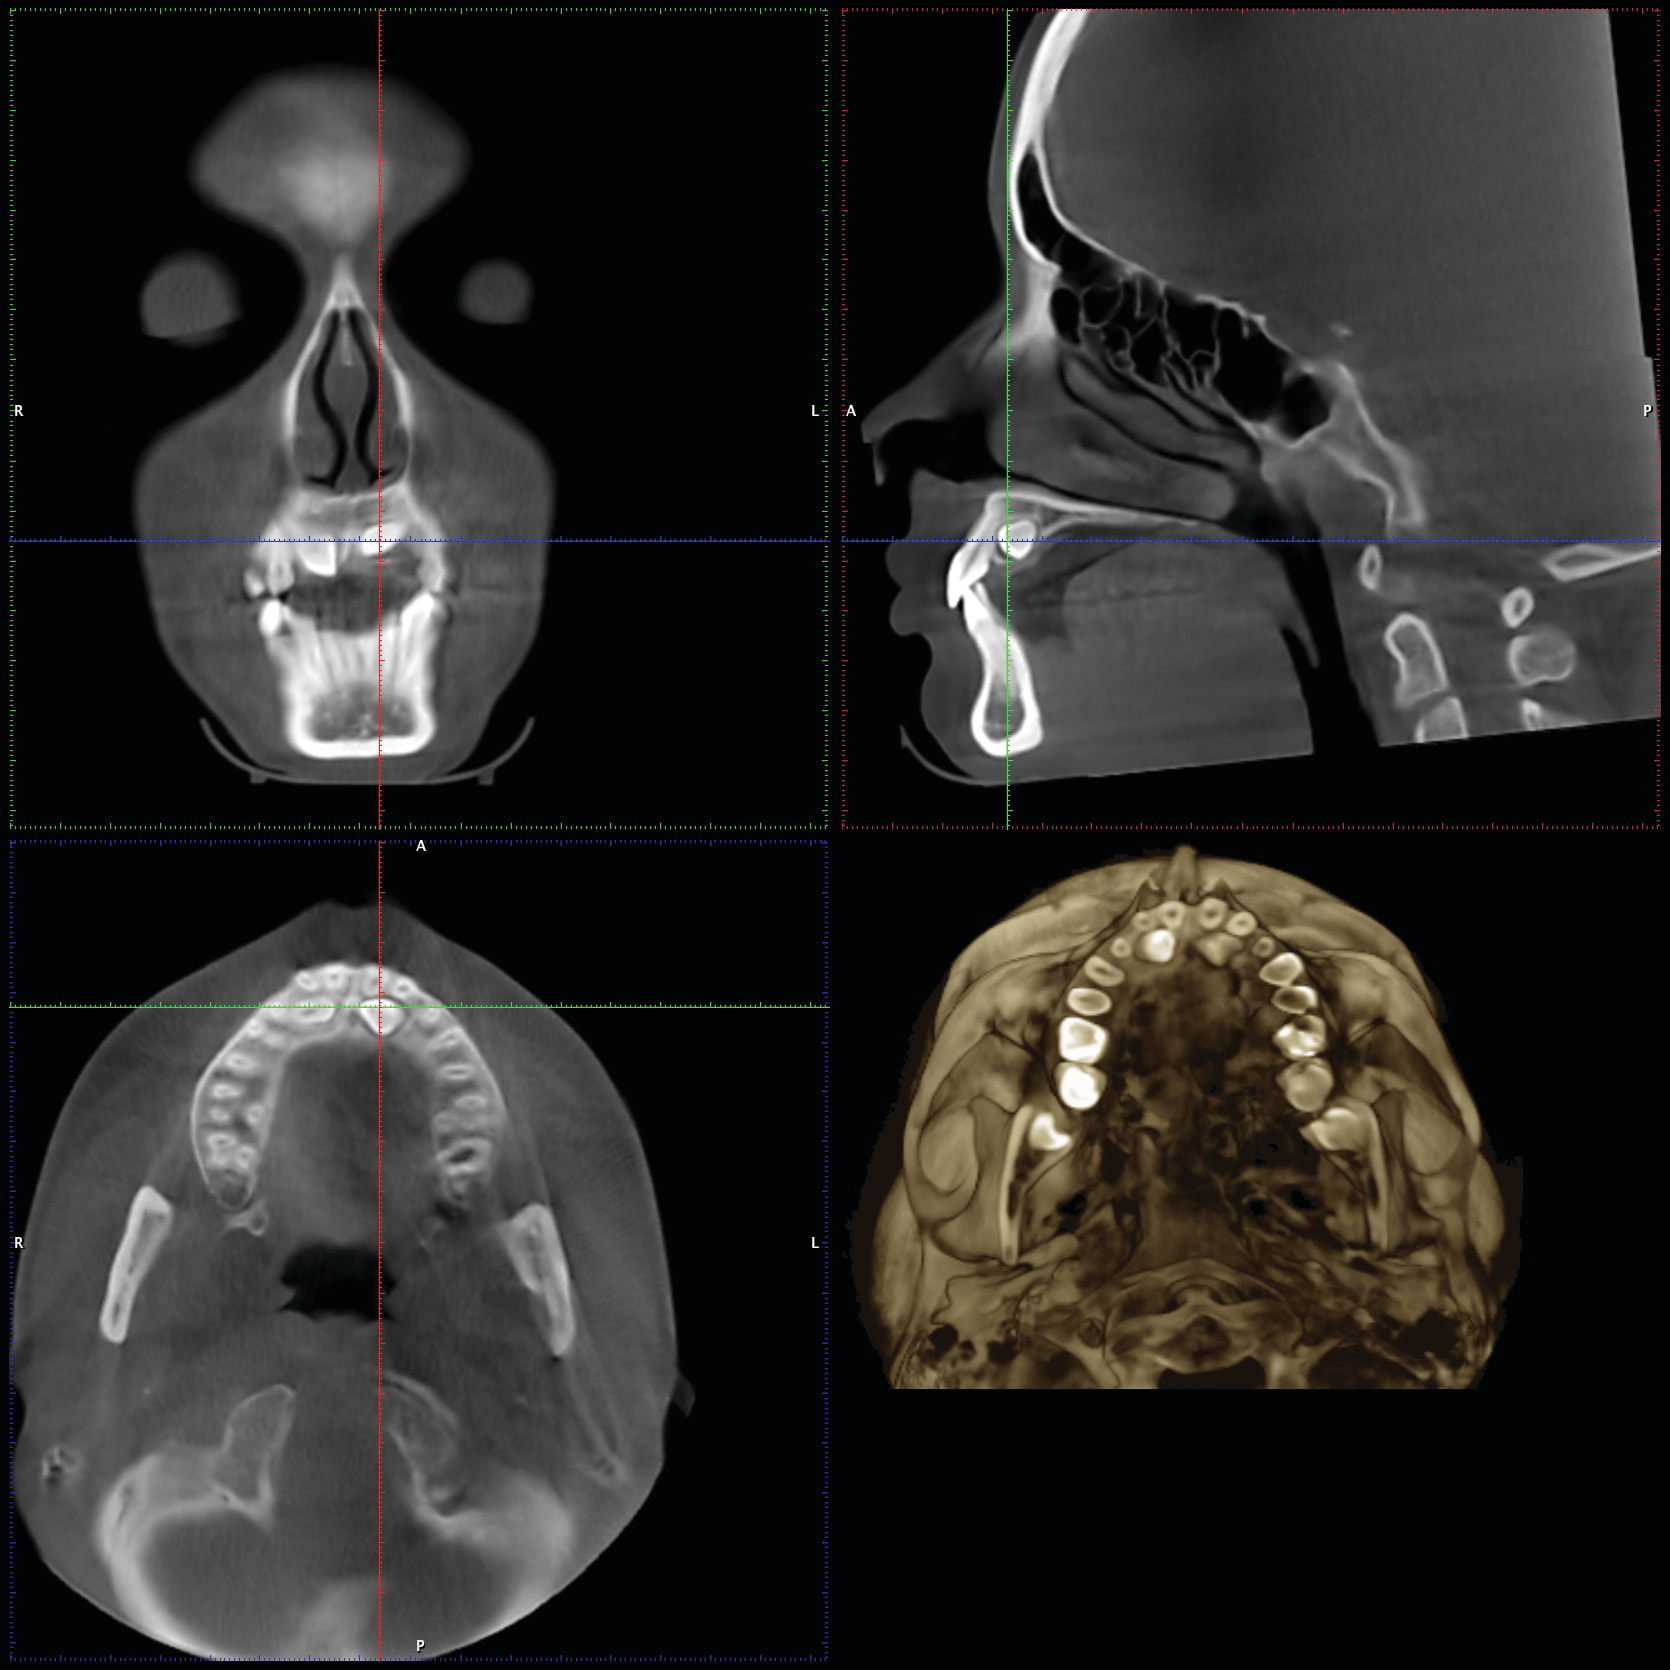

1. Many have advocated that the use of 3D imaging is certainly useful in treating patients with impacted maxillary canines. This is certainly true. However, only 1 to 2 percent of the population has impacted canines. The population of most orthodontic practices is published that 5 percent of the practice’s patients seeking treatment have impacted canines. If this is the main reason for taking DICOM images on patients, then these images should be outsourced. The cost of purchasing a 3D machine for 5 percent of the office’s patients does not make financial sense. A 2-dimensional pan or ceph does not adequately image the impacted teeth for not only surgical planning but also the mechanics needed to move these teeth into alignment. It has been reported that 62% of palatally impacted canines are touching the roots of laterals and centrals. This is information that 3D imaging illustrates. This could often change the mechanics needed to properly position the canines without damaging the roots of adjacent teeth. However, the 3D imaging of impacted teeth certainly is advantageous to the orthodontist or oral surgeon that will surgically expose the non-erupted teeth. This is illustrated in Figure 1 through Figure 3. One can readily see the benefits to the patient for using 3D imaging technology for the treatment of impacted teeth.